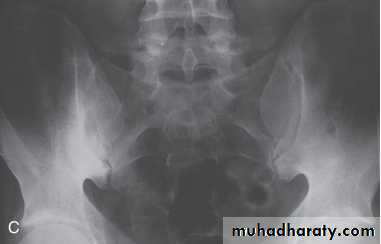

In established AS, radiographs of the sacroiliac joint show irregularity and loss of cortical margins, widening of the joint space and subsequently sclerosis, joint space narrowing and fusion.Lateral thoracolumbar spine Xrays may show anterior ‘squaring’ of vertebrae due to erosion and sclerosis of the anterior corners and periostitis of the waist.

In advanced disease, ossification of the anterior longitudinal ligament and facet joint fusion may also be visible. The combination of these features may result in the typical ‘bamboo’ spine.Erosive changes may be seen in the symphysis pubis, the ischial tuberosities and peripheral joints.

Osteoporosis and atlantoaxial dislocation can occur as late features.

An acute inflammatory oligoarthritis occurs in around 10% of patients with ulcerative colitis and 20% of those with Crohn’s disease. It predominantly affects the large lower limb joints (knees, ankles, hips) but wrists and small joints of the hands and feet can also be involved. The arthritis usually coincides with exacerbations of the underlying bowel disease, and sometimes is accompanied by aphthous mouth ulcers, iritis and erythema nodosum.It improves with effective treatment of the bowel disease, and can be cured by total colectomy in patients with ulcerative colitis.

Enteropathic arthritis